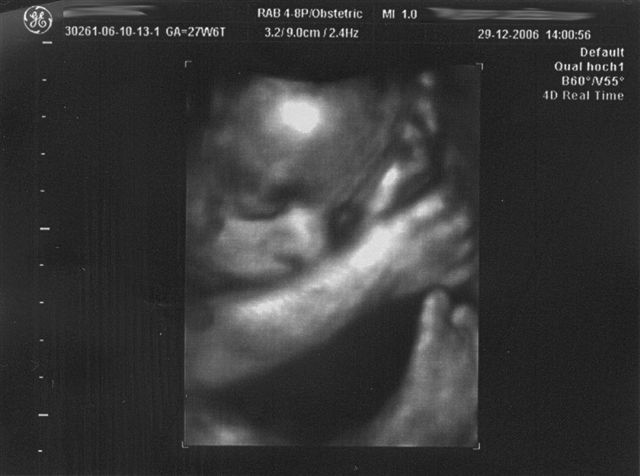

27+6 SSW

Waaaaaahnsinn, was sich in den letzten 7 Wochen getan hat. Richtig Speck hat der Kobold angesetzt. Verschlafen war er heute auch. Das CTG war dem Doc zu "ruhig" - also noch mal mit "Bauchschüttel-Wecken"...."Na also, geht doch" meinte der Doc und war zufrieden.

Beim anschließenden Ultraschall ist u.a. obiges Bild entstanden . Papa und der große Bruder waren mit und beide waren gleichermaßen fasziniert.

Kurzum: Alles dran, alles in Ordnung und absolut zeitgerecht entwickelt. 1.100 g wiegt er schon und ist etwa 25 cm lang, wobei die Länge nur geschätzt ist und nach oben und unten variieren kann.